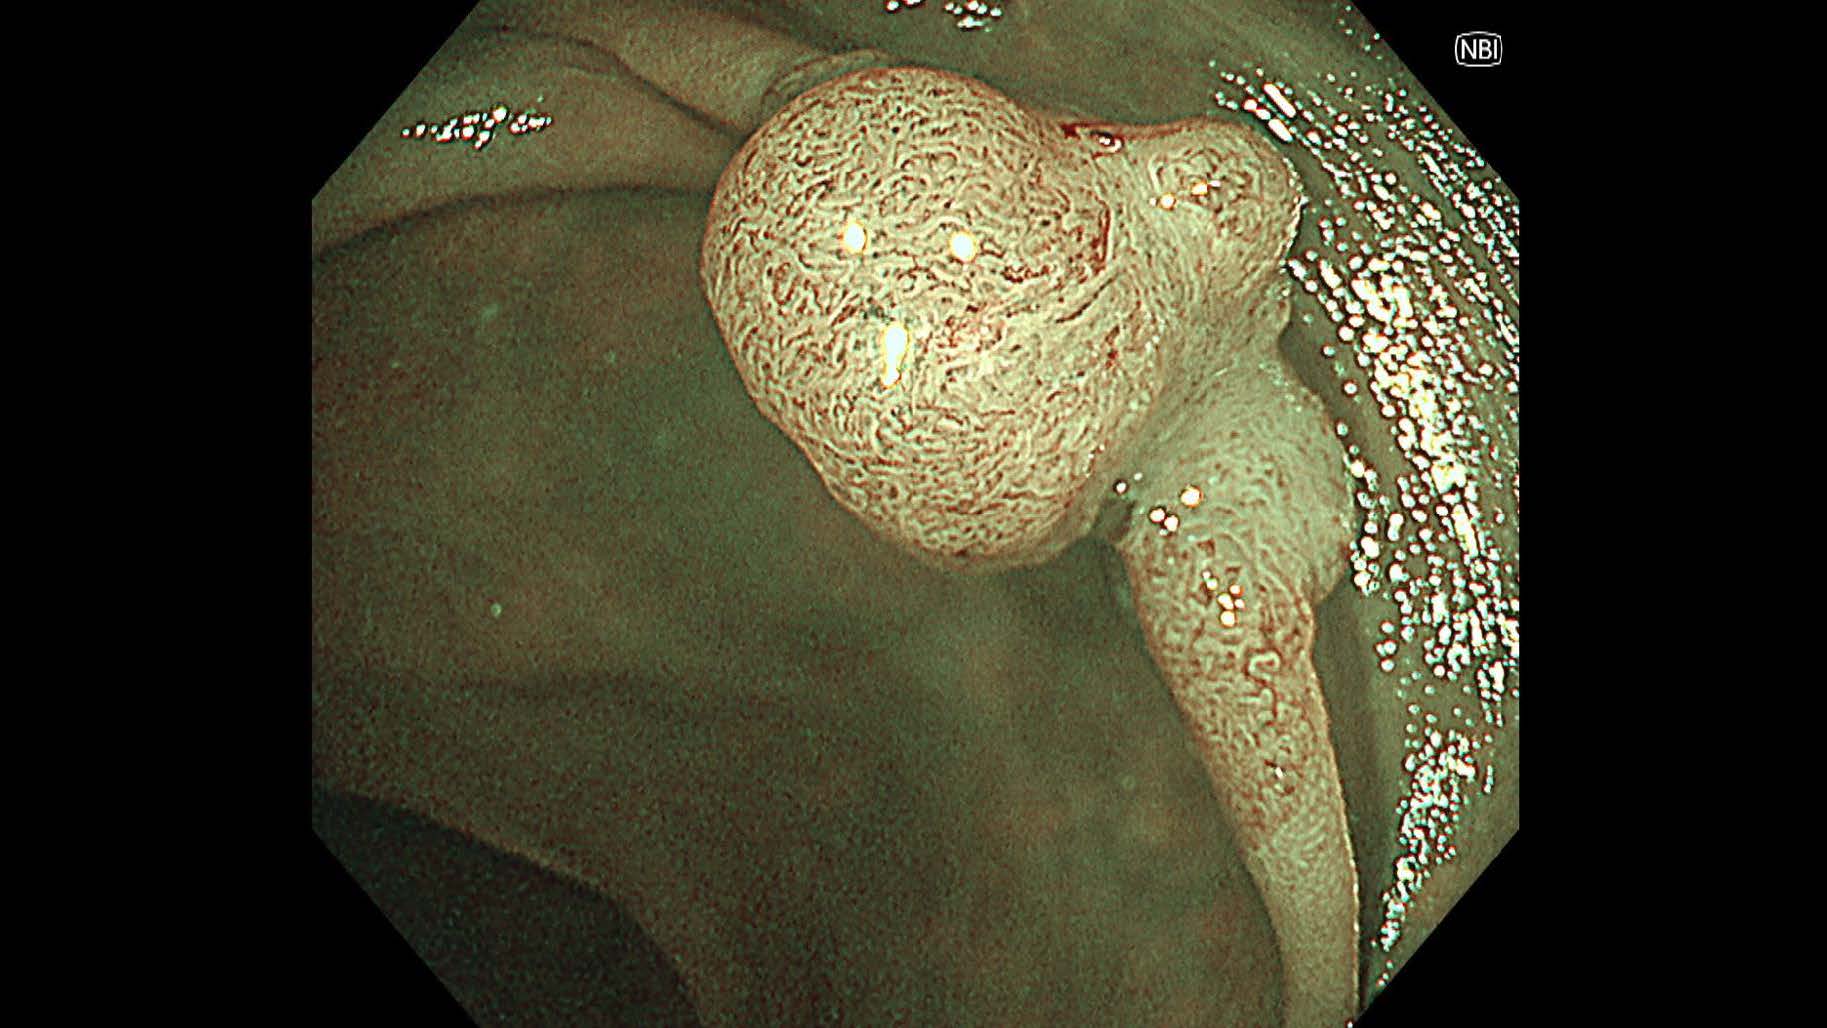

消化管Mapping~大腸~ 2025.6.11

消化管Mapping

消化管Mapping~大腸~

消化器内科

内視鏡検査・治療